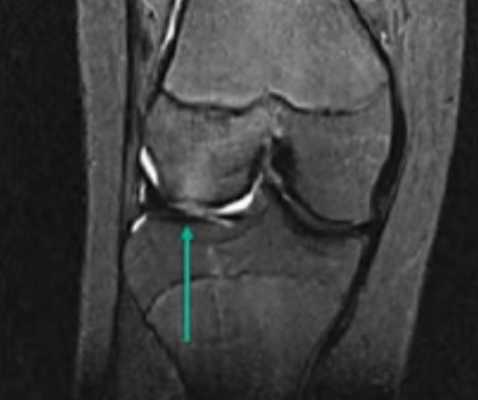

МР-снимок коленного сустава в режиме Т2, контузия кости

Для повышения качества визуализации используют контрастирование. Введение в организм препарата гадолиния обеспечивает более выраженную реакцию атомов водорода на магнитное поле. В результате увеличивается контрастность снимков, появляется возможность выявить мельчайшие очаги патологических изменений и оценить особенности кровообращения в сочленении.